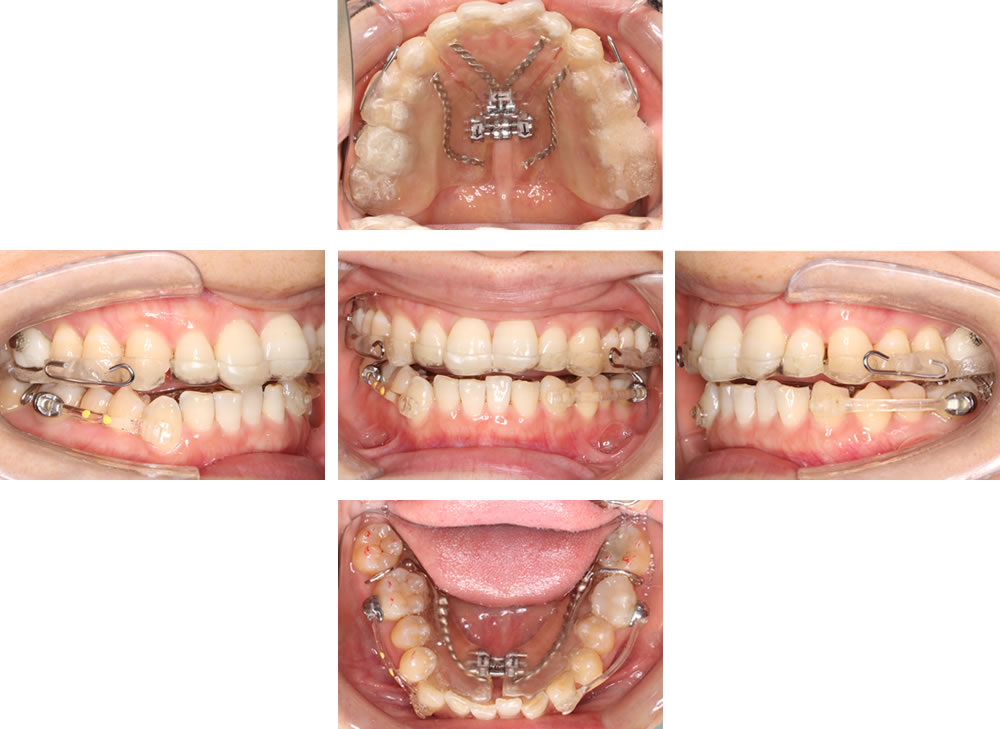

拡大床の装着

拡大床とカリエール(咬み合わせを改善するための矯正装置)を併用し、顎堤の拡大を行うと同時に、咬合の中心となる第一大臼歯の上下の位置関係を改善していきます。